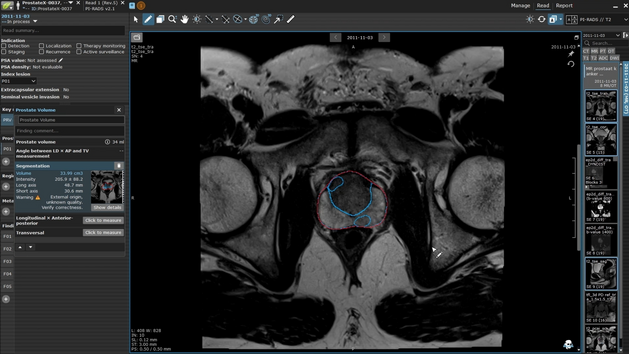

Mint Medical and mediaire strengthen the prostate cancer care pathway with AI-Powered MRI Solutions

Mint Medical, a Snke company, and mediaire announce a collaboration to advance AI‑powered MRI workflows through the interoperability of mint Lesion…